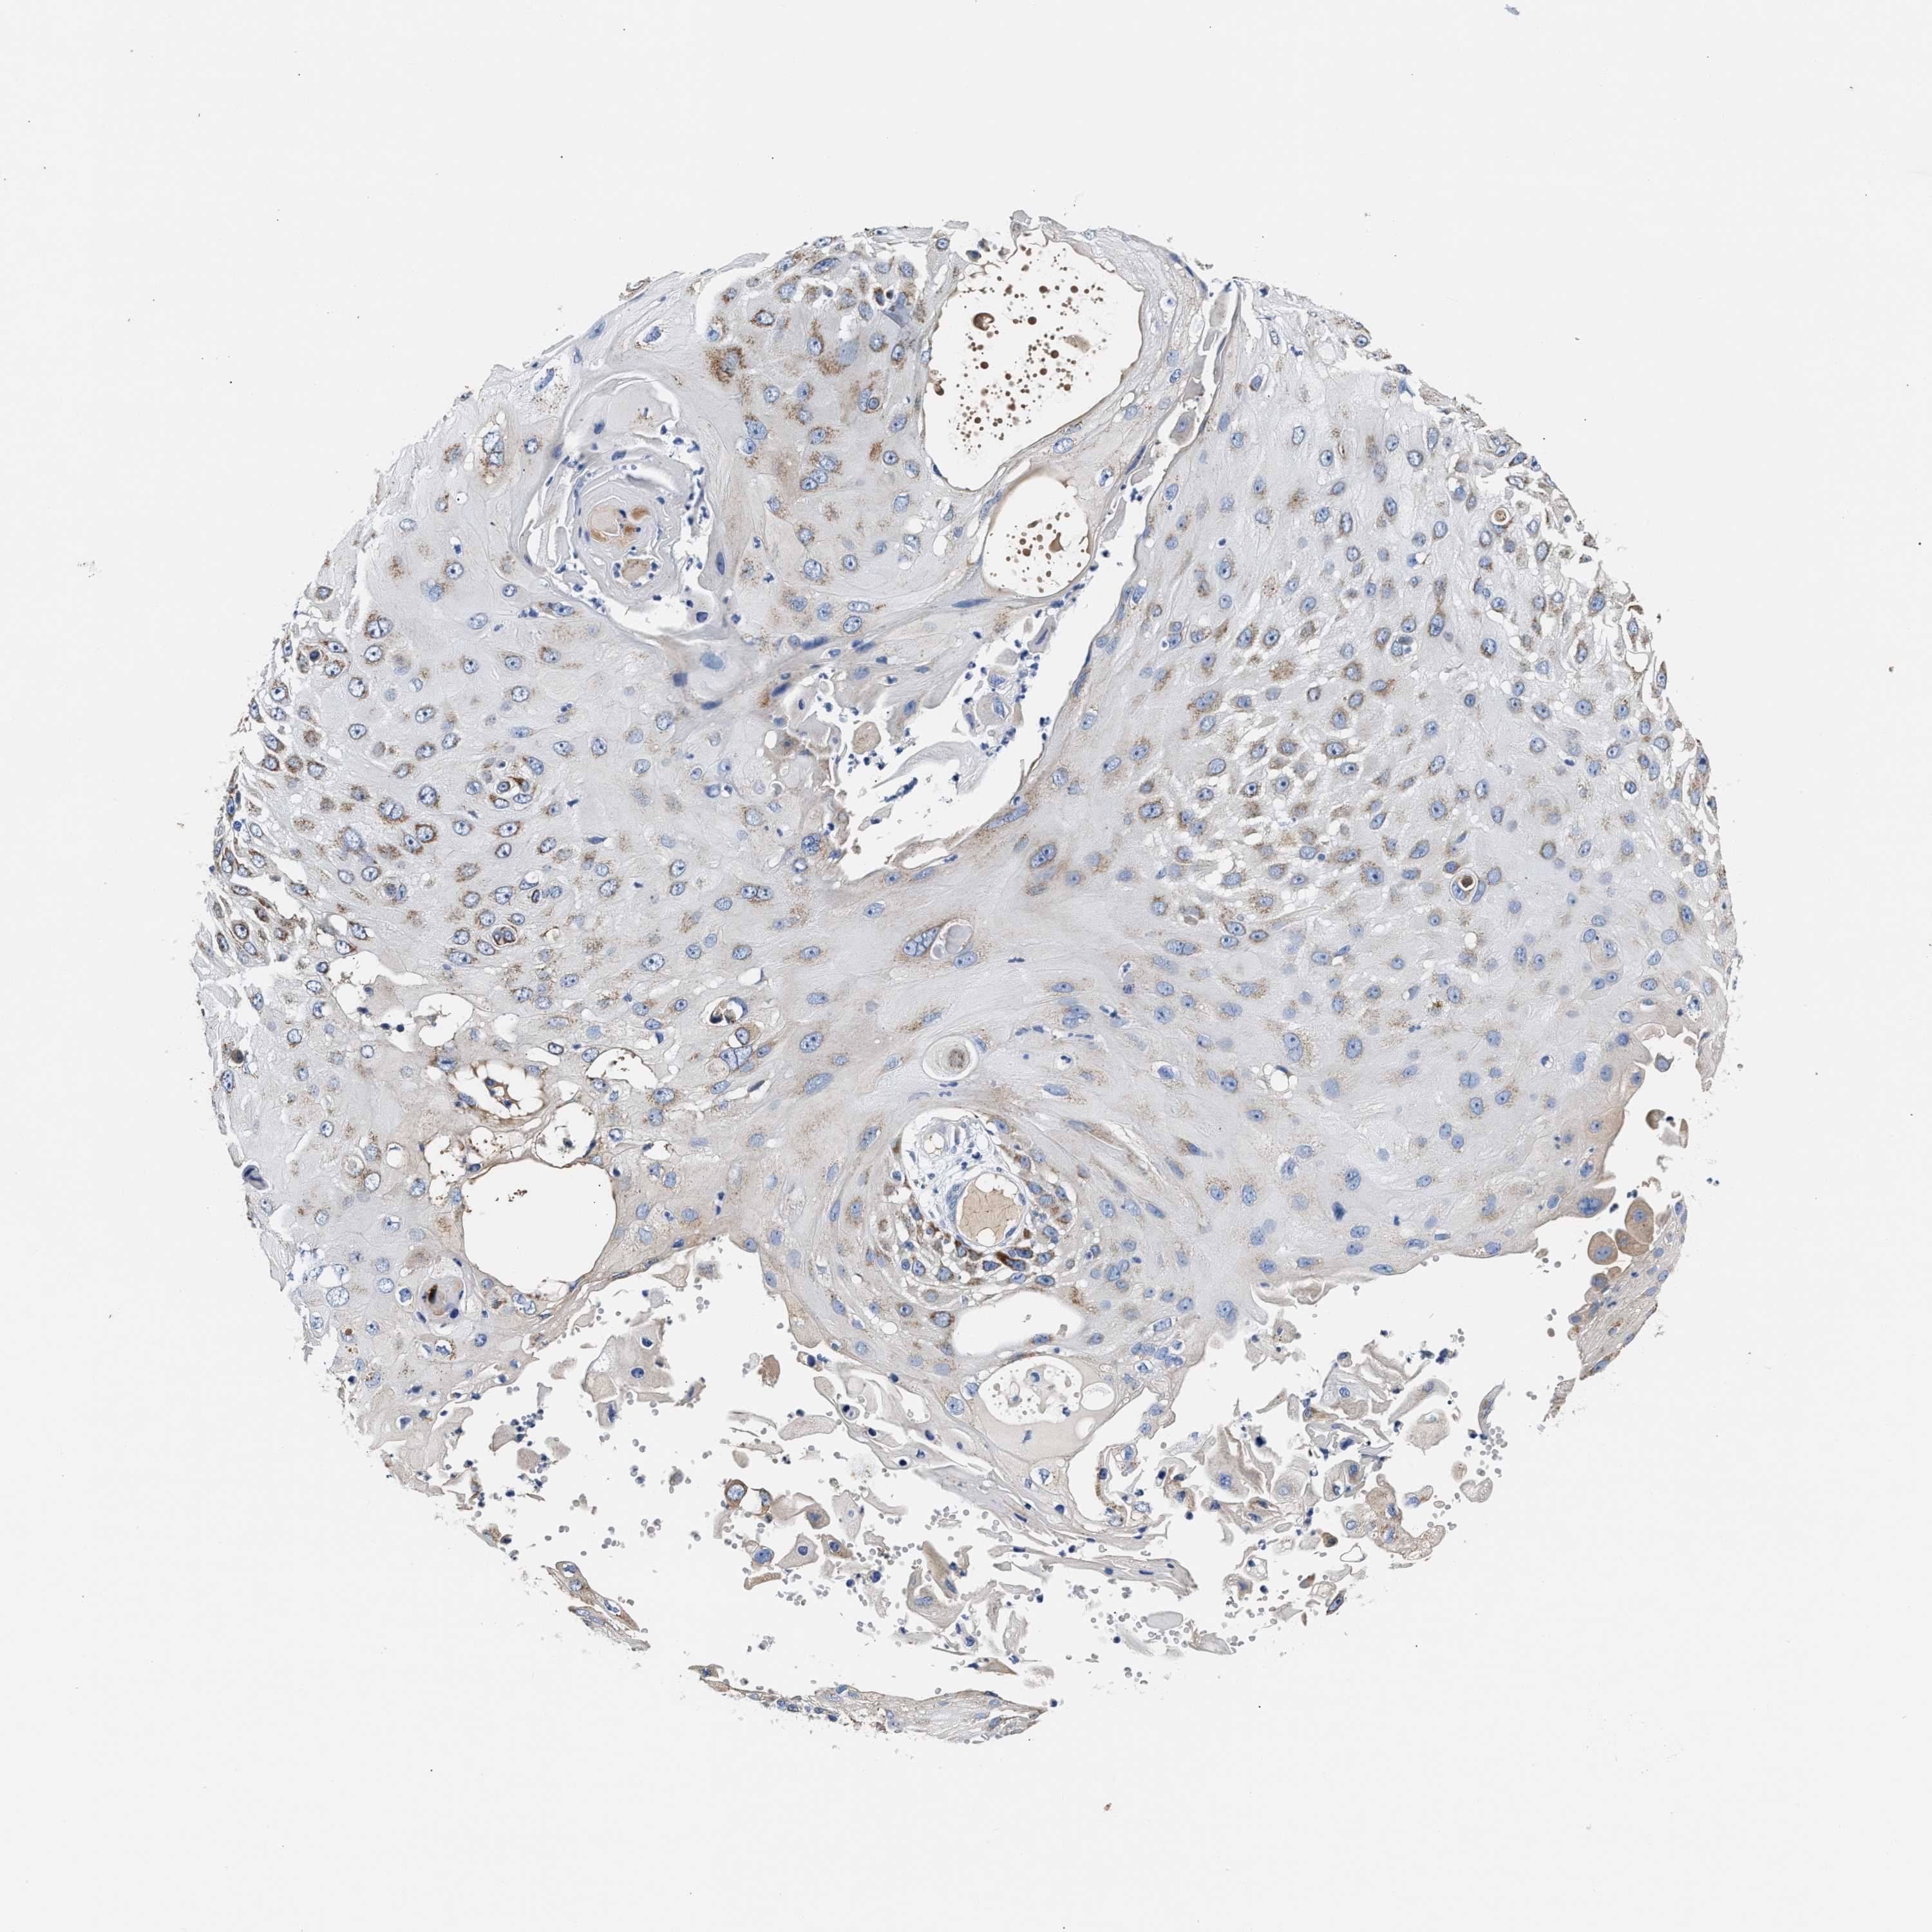

SKIN CANCER - Protein expressioni

A mouse-over function shows sample information and annotation data. Click on an image to view it in a full screen mode. Samples can be filtered based on level of antibody staining by selecting one or several of the following categories: high, medium, low and not detected. The assay and annotation is described here.

Antibody stainingi

Antibody staining in the annotated cell types in the current human tissue is reported as not detected, low, medium, or high, based on conventional immunohistochemistry profiling in selected tissues. This score is based on the combination of the staining intensity and fraction of stained cells.

Each image is clickable and will lead to virtual microscopy that enables deeper exploration of all samples and also displays staining intensity scores, fraction scores and subcellular localization as well as patient and tissue information for each sample.

Antibody HPA020620

Staining

High

Medium

Low

Not detected

Intensity

Strong

Moderate

Weak

Negative

Quantity

>75%

75%-25%

<25%

None

Location

Nuclear

Cytoplasmic/membranous

Cytoplasmic/membranous,nuclear

Squamous cell carcinoma, NOS

Squamous cell carcinoma, metastatic, NOS

Basal cell carcinoma